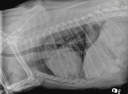

Il nous fait un cinéma ou doit-on l’envoyer en chirurgie ?!?